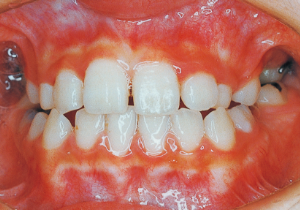

2 After Phase 2 Treatment 5-9-’92

16 5-9-’92 After Phase 2 Treatment

17 8-15-’94 After Retention 14 years and 7 months after start of treatment